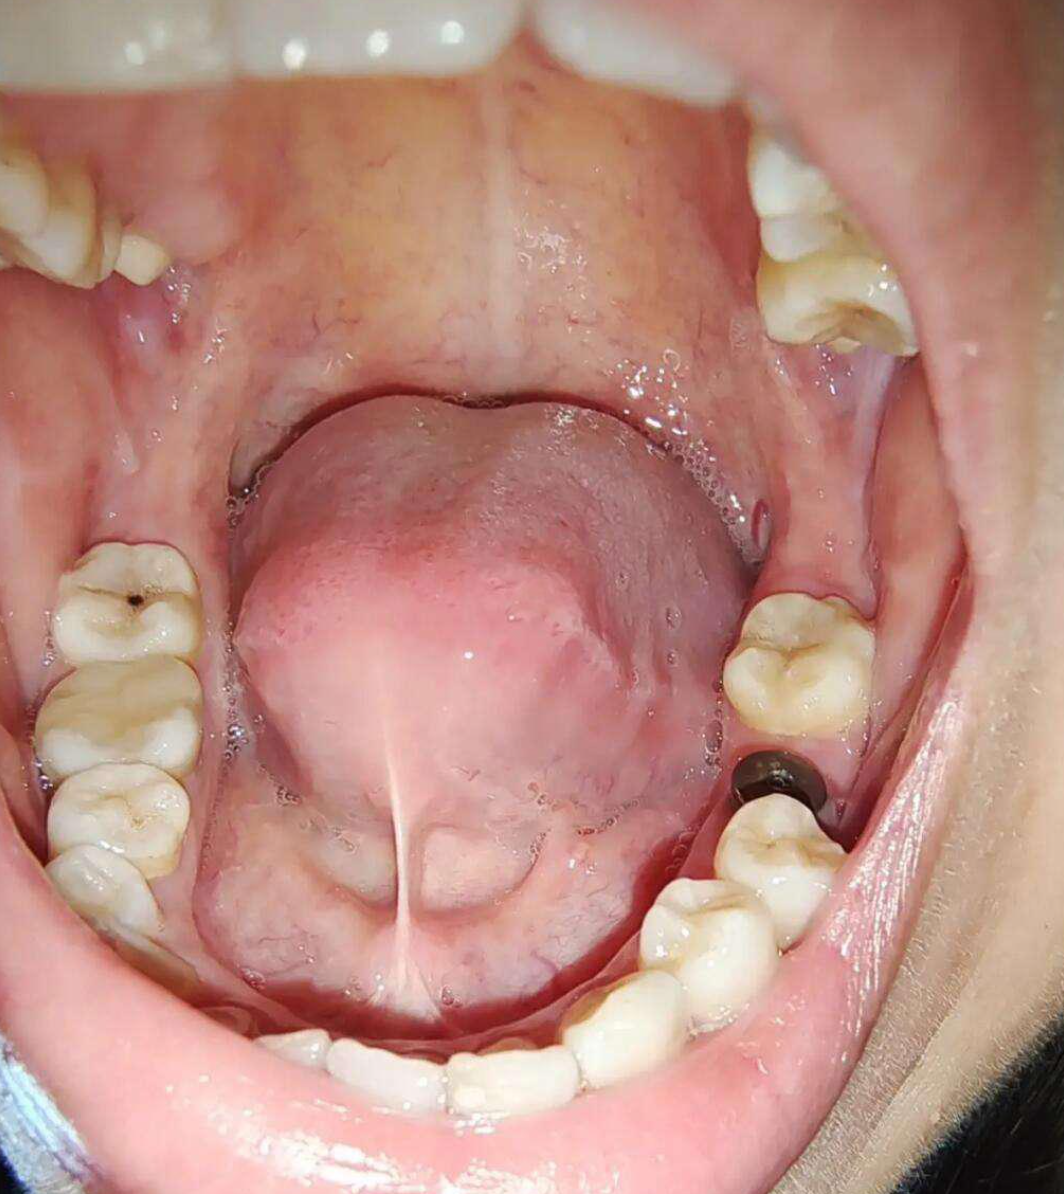

会翘二郎腿的智齿

找了个协和教授,据说已经拔过我这类复杂的30例,我这智齿叫舌向低位